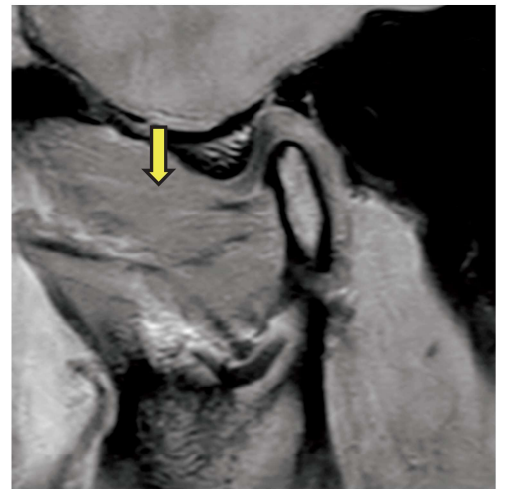

顎関節部 MRI(別冊No. 1)を別に示す。

矢印で示すのはどれか。 1 つ選べ。

解答:d

解説:

黄色の矢印:外側翼突筋